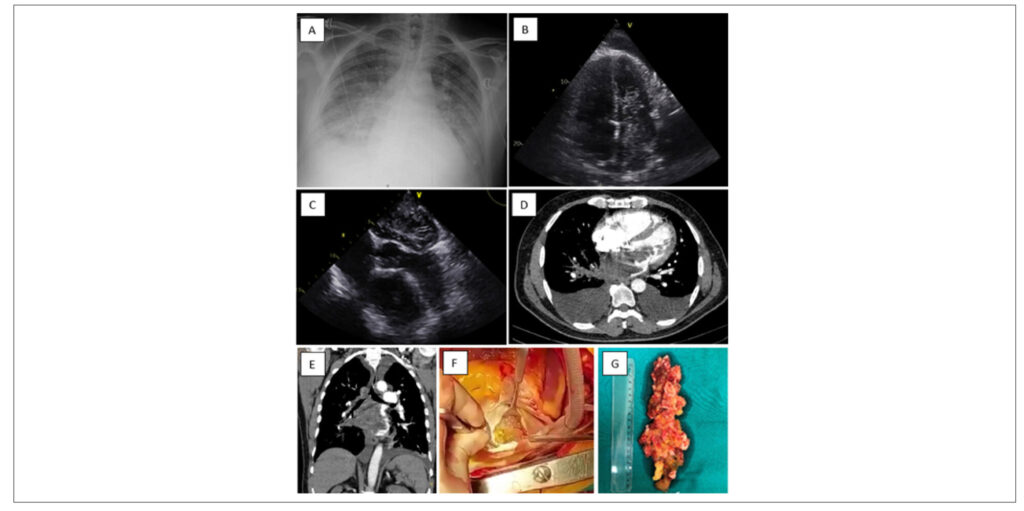

Malignancy of a Benign Tumor

Cardiac tumors can be classified into primary and secondary types. Primary tumors are more common, and the majority of them are benign (70%), with myxomas being the most frequent. However, the overall incidence is rare, ranging from 0.15% to 0.2% in autopsy series. Here we present an image of malignancy of a benign tumor.